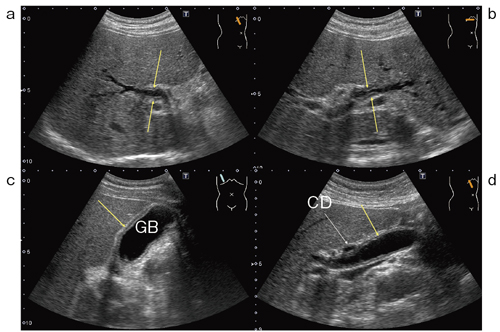

Bモード画像で,膵全体の腫大と低エコー化,膵体部に狭小化した主膵管を認め,自己免疫性膵炎と診断した。胆管をBモード画像で確認したところ,左右肝管合流部から左肝管に向かう部分に壁の肥厚像と狭窄を認めた。また,胆嚢全体の壁肥厚像を認めた。さらに,肝外胆管も拡張しており,これは膵頭部腫大のためと考えた。これらの所見よりIgG4関連の硬化性胆管炎と診断した(図3)。

図3 症例2:IgG4関連硬化性胆管炎のBモード画像

CD:胆嚢管,GB:胆嚢